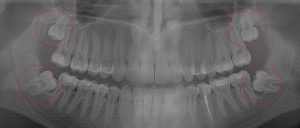

This 19 year old patient has all four 3rd molars present (circled). The roots are +90% formed. Both lower 3rd molars are impacted against the 2nd molars with no chance of further eruption and a +60% probability of decaying before age 30. The patient presented with pain and infection around both lower 3rd molars, requiring immediate extraction